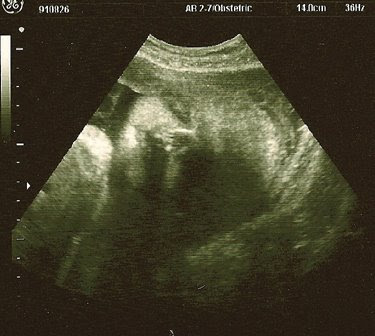

…there’s that sweet little head. We had an ultrasound on Tuesday to take a look at the fluid level around the baby (I had low fluid with E) and they wanted to start a bit earlier in the monitoring. Things looked pretty good this time around – they were looking for the magic number of 10, and we were just above that. We got a free pass for a few weeks, but will begin weekly monitoring after that so we’ll be seeing a lot more of this little one then. After checking and rechecking the numbers, we got to stick around for a little show. Not only was the baby awake, but it was opening and shutting its eyes and mouth – little gestures that reminded us of the way a baby looks right after they wake up and they are just peacefully looking around the room checking things out. We knew from our pregnancy journal that the eyelids were no longer fused, but it was still so strange to see the eyes open and moving. I’m not sure what there is to “see” in there, and the baby has no way yet to process images – but it is clearly practicing all those reflex movements that will help it figure out this world once it enters it. Towards the end of the show the baby yawned the sweetest, most perfect little yawn. It made all those kicks and jabs and uncomfortable moves in the night a little less bothersome once we saw that little one just gently moving and adjusting to its shrinking environment. Why should I complain or gasp every time one of these movements throws me off balance or connects with some tender organ of my own – look at this sweet little thing in there, just practicing those muscle movements and trying to find some space?